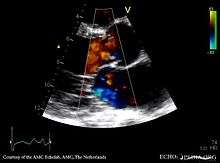

In terms of the diagnosis of aortic regurgitation a common test for the evaluation of the severity is transthoracic echocardiography, which can provide two-dimensional views of the regurgitant jet, allow measurement of velocity, and estimate jet volume.[17] The findings in severe aortic regurgitation, based on the 2012 American College of Cardiology/American Heart Association guidelines include:[18][19]

- An AI color jet width > 65 % of the left ventricular outflow tract diameter

- Doppler vena contracta width > 0.6 cm

- The pressure half-time of the regurgitant jet is < 200 ms

- Early termination of the mitral inflow

- Holodiastolic flow reversal in the descending aorta.

- Regurgitant volume > 60 ml

- Regurgitant fraction > 50 %

- Estimated regurgitant orifice area > 0.3 cm2

- Increased left ventricular size